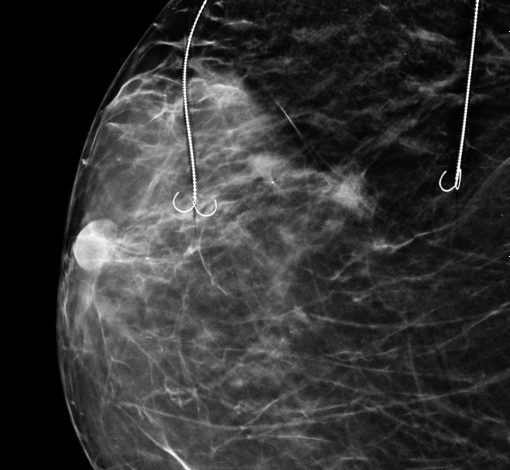

În cadrul Secției Chirurgie I, coordonată de Prof. Univ. Dr. Răzvan Popescu, a fost realizată în premieră o intervenție chirurgicală de conservare a sânului în cazul unei paciente cu trei leziuni maligne, prin tehnica Bracketing cu două harpoane.

- Alexandru Gavrilă – medic primar radiologie și imagistică medicală, competență în senologie